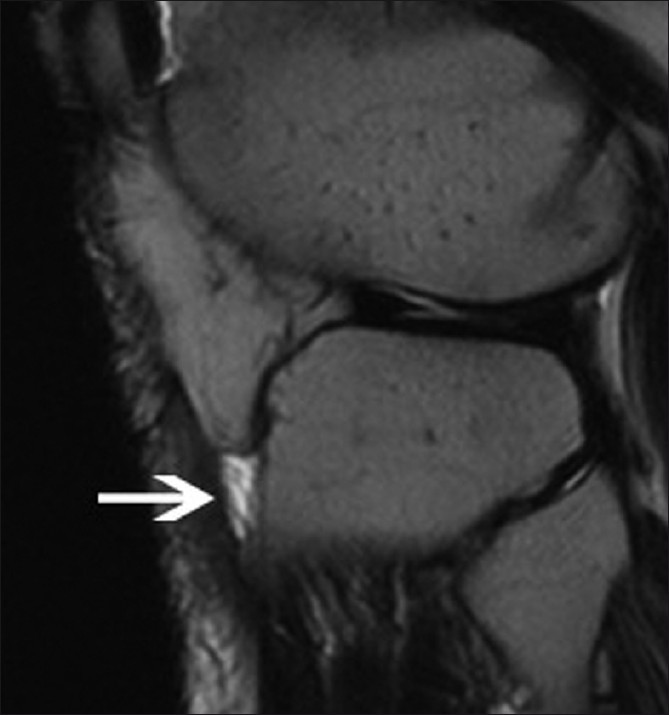

대부분의 정상적인 점액낭은 소량의 점액을 함유하여 MRI에서 잘 관찰되지 않지만, 염증성 변화에 의해 점액양이 증가되면 T1 영상에서 저신호 강도를, T2 영상에서 고신호 강도를 보이는 경계가 명확한 점액낭이 관찰된다.

하지만 슬와근 열공측측부인대 점액낭(Voshell's bursa)의 경우에는 정상 관절에서도 MRI 검사 시 흔히 나타나므로 각각 외측 반월연골판의 후각부 파열과 내측측부인대 파열로 오진할 수 있으므로 병적 상태와 감별을 요한다.

△ 내측측부인대 점액낭염 (Voshell's Bursitis)

(이미지 출처 : http://radiologycases.blogspot.kr/2010/08/voshells-bursitis.html)